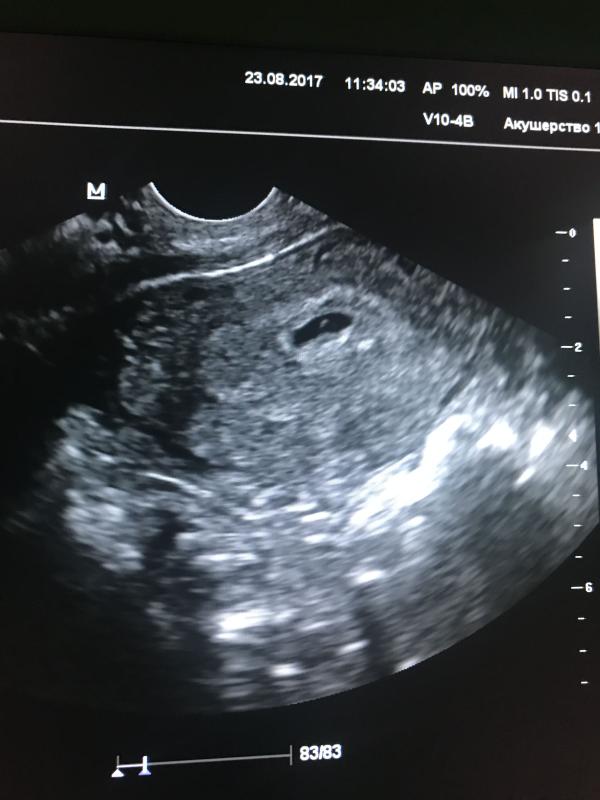

Сегодня была на первом УЗИ. Хорошо видно плодное яйцо и малютку эмбриона 3мм. Через недельку пойдём слушать сердечко ❤️

23.08.2017